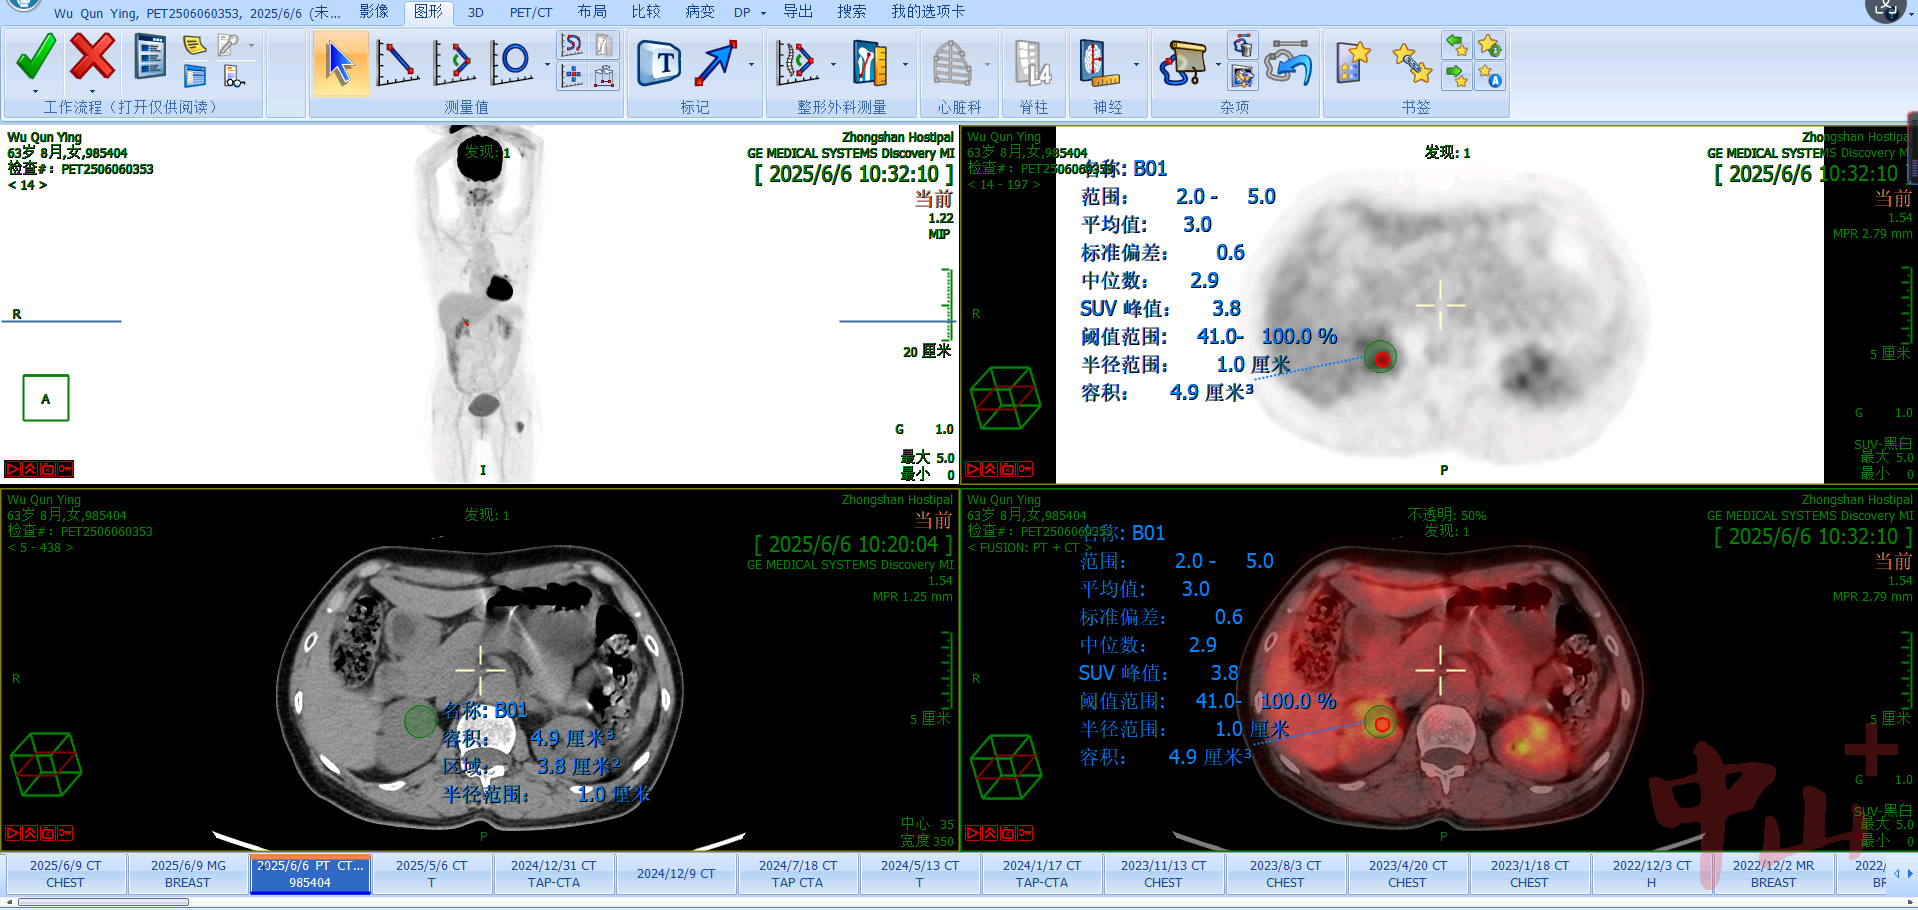

另外,该影像集成平台运用在影像诊断时,PET-CT/MR融合可同时清晰显示病灶形态、大小、位置及代谢活性;运用在放疗计划时,可辅助医生精确勾画生物靶区,在融合图像上区分肿瘤组织与周围正常组织或危及器官,提高放疗的精度,减少副作用。

而当该平台应用在疗效评估时,医生通过治疗前后不同时间点的多模态影像融合对比,可直观、定量地评估患者的治疗效果。比如腹主动脉瘤术后复查后,通过该影像集成平台,医生可直观监测患者术后是否有内漏发生等。